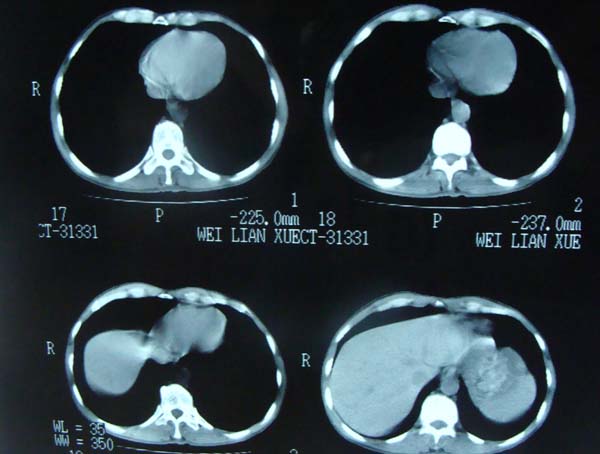

以下是引用pujunzhi在2009-6-21 21:48:00的发言:[br]右肺上叶后段见一空洞性病灶,灶周有渗出即晕征,右肺门肿大---可考虑感染性空洞和癌性空洞,先抗炎抗痨后复查并完善相关检查。有癌性空洞伴肺门淋巴结转移的可能。